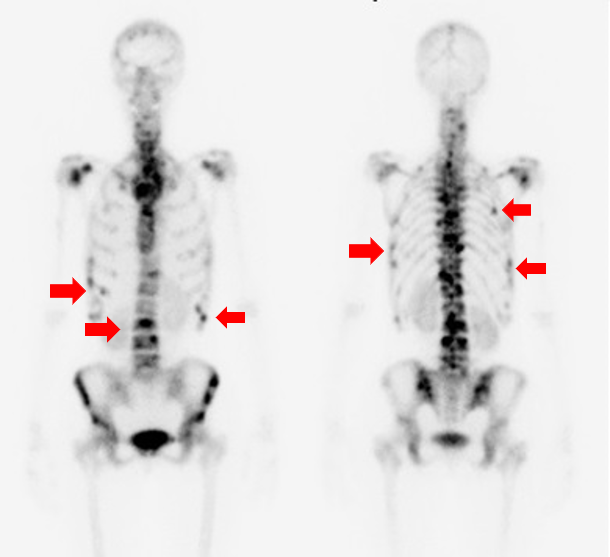

●脳流血シンチグラフィ

脳流血シンチグラフィは、脳にある血管の血流量を調べる検査です。脳流血を反映する薬剤を投与し、脳血流が豊富なところを赤色で、血流が乏しくなっているところを青色で表示して画像化します。

下に提示した症例は、脳梗塞を発症した患者さんの、核医学とMRI画像です。左図の脳血流シンチグラフィ画像では、画像左側が緑や青色で表示され、脳血流が低下していることが分かります。中央の画像では、脳血流が低下しているところが白く描出され、右図の脳血管を描出したMRI画像では左の脳動脈は描出(青矢印)されていますが、右の脳動脈は描出されていません(赤丸)。